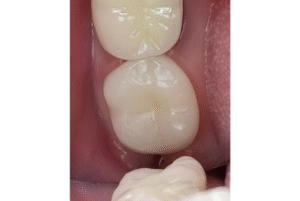

セラミック

e-maxクラウンset

この症例を見る